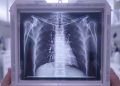

Cambiamenti climatici, inquinamento atmosferico e salute respiratoria: dalla diagnostica molecolare alla gestione delle allergie respiratorie